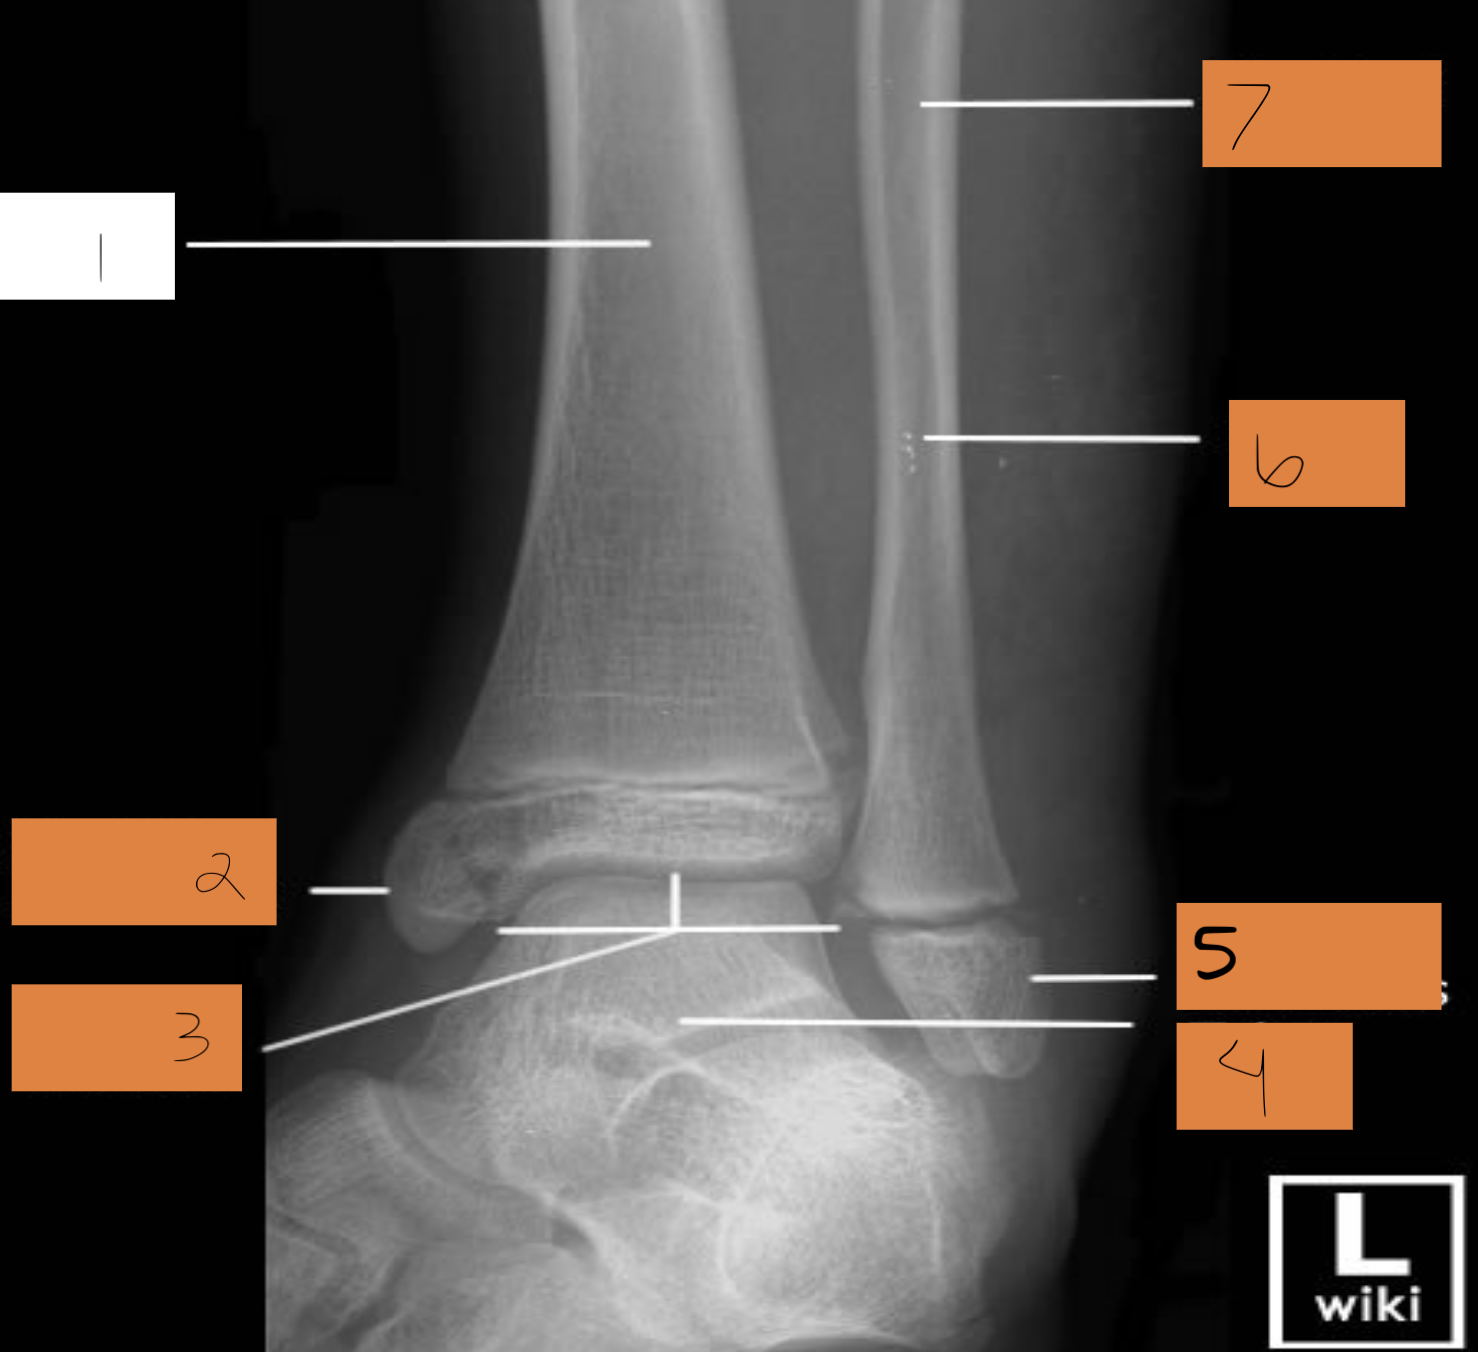

1

distal phalanx

2

middle phalanx

3

proximal. phalanx

4

sesamoid bones

5

metatarsals

6

cuneiforms

7

cuboid

8

navicular